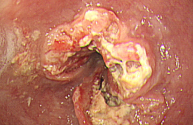

진행성 위암